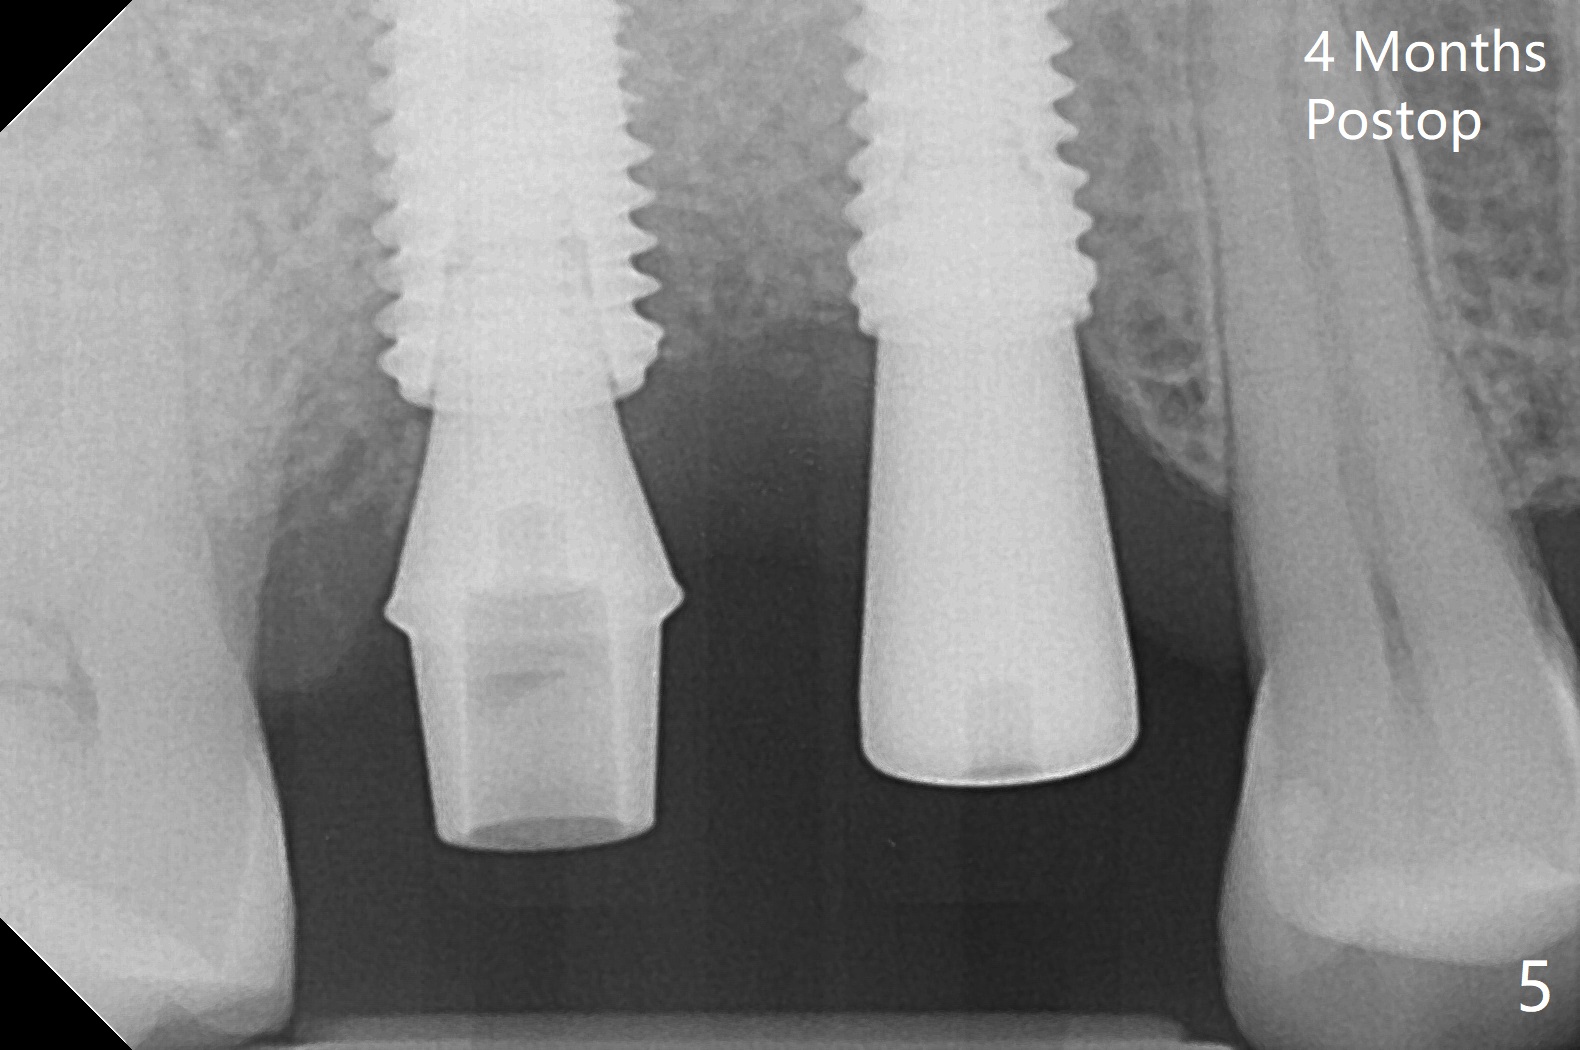

When the tooth #3 with severe buccal gingival recession is extracted and implants are placed at #3 and 4 with guide, sticky bone in 2 large pieces is packed between these implants with a previously large defect in a seemingly secure manner (Fig.1 *). Use of a longer implant at #3 (11.5 mm vs. 10 mm) will reduce the chance of abutment screw loosening in the future. With 2 pieces of PRF membrane coverage, an immediate provisional is fabricated for graft retention (Fig.2,3 P). To stabilize a buccal flap (Fig.2 *, used to be buccal furca gingiva), periodontal dressing is applied later. The buccal socket heals 12 days postop (Fig.4). Apparently new bone forms between the implants 4 months postop (Fig.5). The abutment at #3 may not be completely seated. In fact it is loose, probably related to buccal gingival and gingival cuff erythema 6.5 months postop (Fig.6). Large healing abutments are placed to form the interdental (interimplant) papilla without effect (*). Provisional crowns will be fabricated for the papilla formation. When cemented abutments are placed (Fig.7), papilla formation by manipulation of provisional crowns seems unlikely. Impression is taken. Although there is no implant thread exposure, the buccal plate is concave 7.5 months postop (Fig.8). With special crown design, food impaction should be minimal post cementation (Fig.9,10). There is no bone loss 5.5 months post cementation (Fig.11), while the soft tissue is healthy (data not shown).